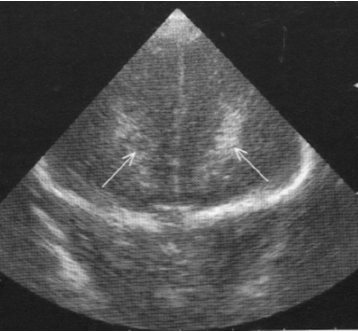

Neonatology Grade 1 PVL 2 Image